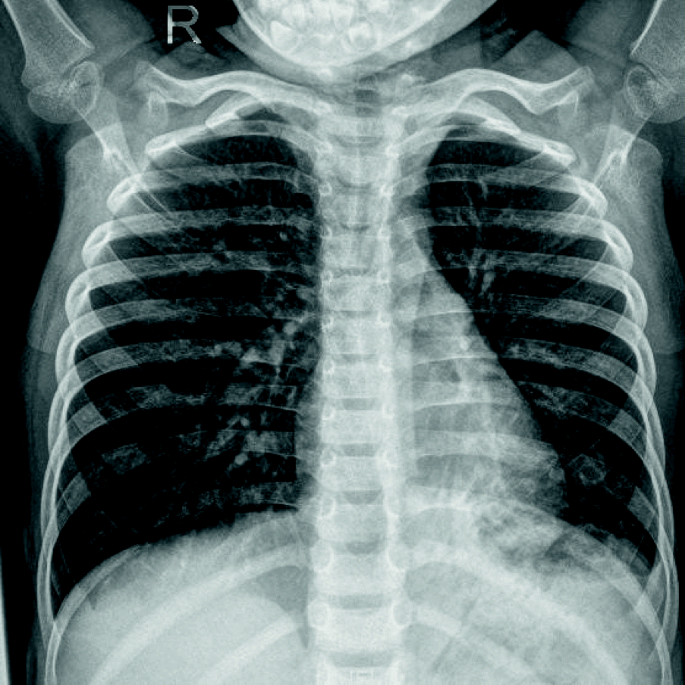

A previously healthy 3-year-old girl was admitted to Xiamen Children’s Hospital after a 5-days history of fever and cough. At the local hospital, she was prescribed intravenous azithromycin for 2 days, but the temperature elevated again. On the day of admission, she had cough, fever (38.0 °C), shortness of breath, breath sounds of the left lower lung decreased, and we could hear moist rales and a little wheezing. The WBC count was 14.44 × 109/L (normal ranges: (4–10) × 109/L), her C-reactive protein level was normal, her procalcitonin level was elevated at 7.03 ng/ml, and lactate dehydrogenase was 743 U/L; A chest radiograph showed atelectasis of the left lower lung (Fig. 1). A chest CT scan showed segmental consolidation of the left lower lung and a small amount of effusion in the left thoracic cavity. Coagulation function shows elevated D-dimer and fibrinogen. Mycoplasma pneumoniae-IgM (MP-IgM) > 1:320. Nasopharyngeal swab was sent to the laboratory and Seven respiratory virus antigen tests (influenza A and B, parainfluenza 1, 2 and 3, respiratory syncytial virus and adenovirus) were negative. She received supplemental oxygen and antimicrobial treatment included azithromycin, and cefoperazone sulbactam sodium, all started immediately on admission. But her fever and cough persisted. On the 4th day of admission (the 9th day after the onset of the disease), we performed for her a flexible bronchoscopy, which revealed a whitish rubbery material occluding the left lower lobe bronchus, and plastic casts were removed (Fig. 2). The plastic casts were composed of inflammatory necrosis and neutrophils (Fig. 3). Genetic test for adenovirus serotype 7 in bronchial lavage fluid was positive. Two days after the bronchoscopy, the shortness of breath was improved, but the body temperature was still high. So we gave him gamma globulin (2 g/kg) to regulate immune function, on the 7th day of admission (the 12th day of the disease) her temperature was normal, coughing was alleviated, and discharged from the hospital 1 week later. One week after discharge, the chest radiograph showed that the left lower lobe consolidation was significantly better than before (Fig. 4).

A previously healthy 2-year-old boy was admitted to Xiamen Children’s Hospital because of a repeated fever for 1 month and cough for 20 days. At the local hospital, he was prescribed azithromycin, amoxicillin sulbactam against infection, but fever reccurred again after 5 days of stable temperature. On admission, the child was noted to have a normal breathing pattern and there were no auscultatory signs of note. His WBC count, C-reactive protein and procalcitonin level was normal, and lactate dehydrogenase was 602 U/L; bacterial cultures of blood and sputum were negative. The assay of specific IgM antibodies to seasonal influenza A and B, parainfluenza 1, 2 and 3, respiratory syncytial virus and adenovirus by enzyme immunoassay were all negative. MP-IgM also showed negative result; a chest X-ray showed both lungs were under-polarized, and the lungs were scattered with spots, patchy high-density shadows, and blurred borders. Antimicrobial treatment included ceftriaxone, and oseltamivir, but his temperature was still uncontrolled, and he gradually had difficulty breathing, his breath sounds over the left lower lung were decreased, and moist rales could be heard. The second chest radiograph showed that there was a atelectasis in the left lower lung (Fig. 5). And his C-reactive protein level was elevated (35.5 mg/L), procalcitonin level was elevated (3.71 ng/ml). Immediately, he received supplemental oxygen, cefoperazone sulbactam sodium for infection, gamma globulin (2 g/kg) to regulate immunotherapy and methylprednisolone (1 mg/kg twice daily) to inhibit inflammatory response. A couple of days later, despite subsistence of fever, shortness of breath persisted and a flexible fibre-optic bronchoscopy along with bronchial lavage, revealed a complete obstruction of the left inferior lobar bronchus by thick secretions (Fig. 6). Histologic examination of the plastic casts revealed a large quantity of inflammatory necrosis and neutrophils and a small number of lymphocytes (Fig. 7). Genetic test for adenovirus serotype 7 in bronchial lavage fluid was positive. After bronchoscopy, the shortness of breath was improved. A follow-up chest radiograph returned to normal (Fig. 8).

PB can occur in previously healthy children, although patients with allergy or asthma are at high risk of PB [6, 7]. Our patients had no history of atopy such as atopic dermatitis, allergic rhinitis and asthma. We reported 2 cases of PB associated with adenovirus serotype 7 who had acute onset, repeated fever and cough. Chest radiograph showed atelectasis. We finally diagnosed and cured PB through bronchoscopy. Removal of bronchial casts alone may not result in complete recovery and additional therapy involving gamma globulin infusions and systemic corticosteroids may be warranted.